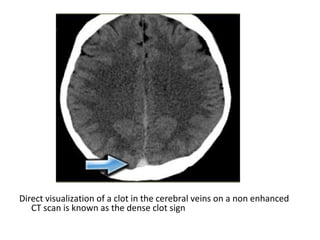

Direct visualization of a clot in the cerebral veins on a non enhanced

CT scan is known as the dense clot sign

Dense clot sign in a thrombosed cortical vein